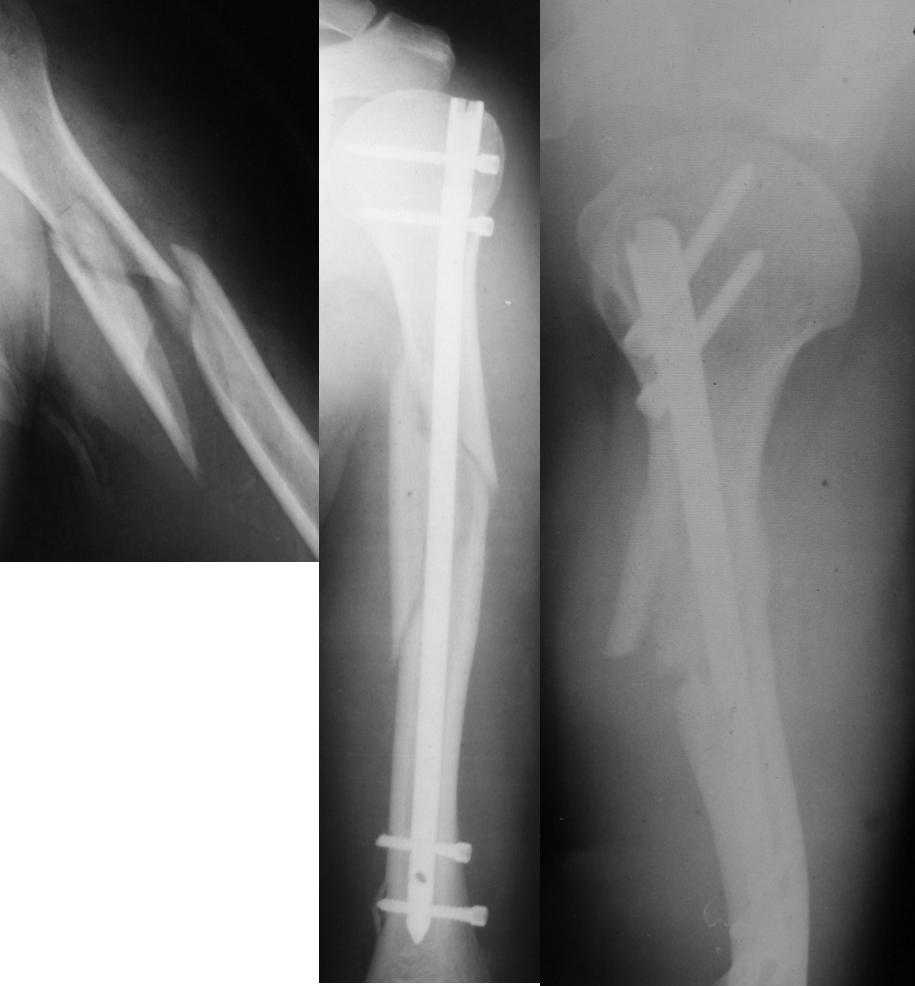

Уважаемые коллеги! Необходима консультация.Больной 52 лет.Травма 02.10.2007г.Операция-19.10.2007г.

Сразу после операции-нарушения кожной чувствительности по наружной поверхности н\3 предплечья,кисти,1 и 2 пальцев кисти,ограничение активных движений в лучезапястном суставе при сжатом кулаке.При электромиографии-лучевой нерв 4% от нормы. Через два месяца после операции беспокоят боли в месте перелома в покое и при движениях в плечевом суставе. Отсутствие положительной динамики в восстановлении кожной чувствительности и объеме движений в л-з суставе.